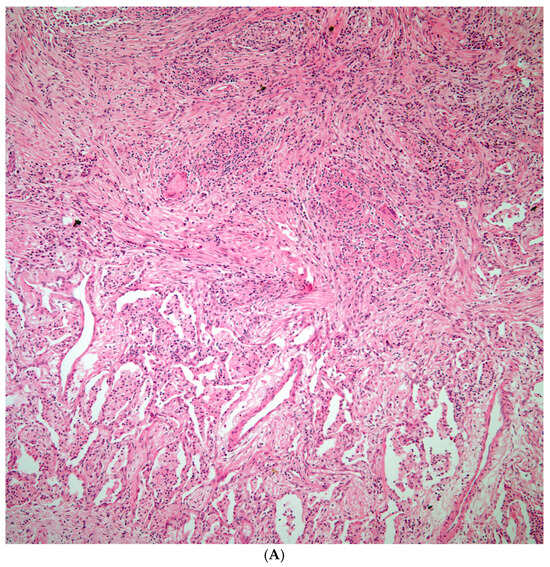

Blastomycosis spp.: The lung parenchyma was replaced by extensive areas of necrosis. Histochemical stains for GMS show the presence of broad budding yeast morphologically compatible with Blastomyces spp. (Figure 4A,B).

Figure 4.

(A) Necrotizing granulomatous inflammation destroying lung parenchyma. (B) GMS shows scattered broad-based budding organisms morphologically compatible with Blastomycosis spp.